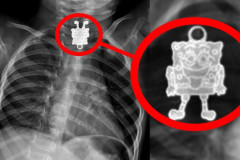

30 Մարտ, 2016 15:17

Աղջկա որովայնին հայտնաբերվածը շոկի ենթարկեց բժիշկներին (տեսանյութ)

Ինչի՞ կարող է հանգեցնել բժիշկների խորհուրդներն անտեսելը. Այս նյութը նյարդերից թո...